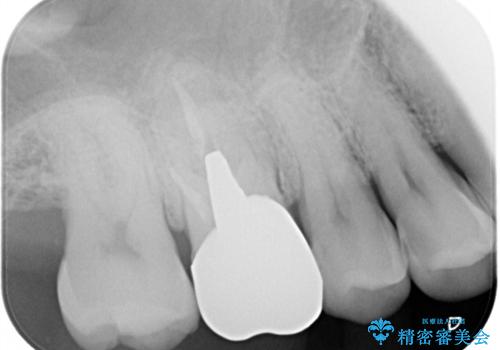

左上の仮歯を2年使用して穴があいて外れたことをきっかけにご来院されました。

レントゲン上からも、歯の中(根管)が汚れている可能性があることをご説明したところ、根管治療からやり直しをすることになりました。